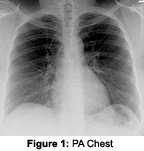

The lateral chest view is taken with a non-grid technique, using a 14 x 17 cassette at 72" film focal distance at a kVp of 100 to 110, with a time commensurate with patient's thickness. Collimation is again a little less than the film size and, in general, there is no need to change the position of the cassette from the PA view. For both views, the central ray is at about T6. In general, the left side always is the side closest to the cassette. The X-ray is again taken on inspiration.